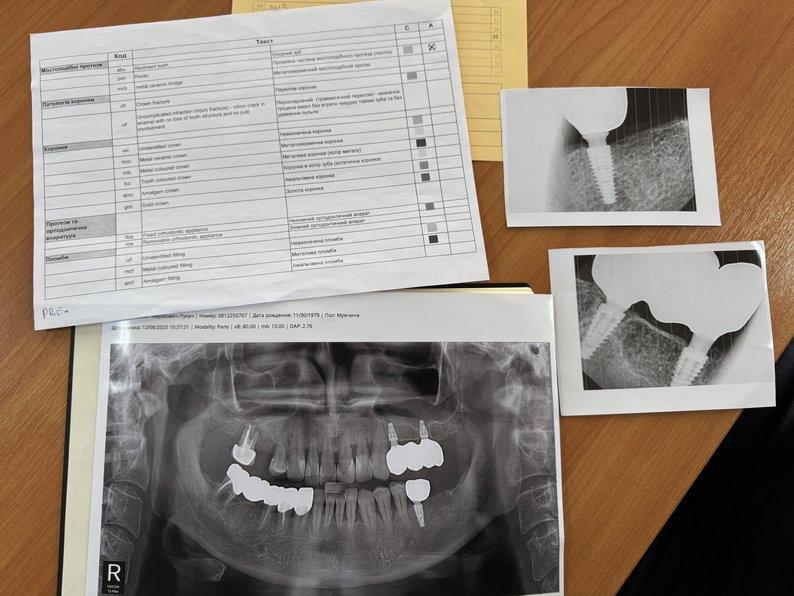

"На початку курсу кожен із нас зробив ортопантофотограму або як їх у народі називають панорамні рентгенограми нижньої щелепи. І, відповідно до таблиці міжнародної, де є всі позначення, тут описано англійською мовою перші три букви, а далі йде український коментар. Згідно з цією таблицею ми складували такий бланк анте-мортем (прижиттєвий — ред.). Тобто дентальний статус зниклого безвісти", — розказав працівник Закарпатського бюро судово-медичної експертизи.

"Це — рентгенологічний апарат, який може створювати як панорамний знімок 2D, так і конусно-променевий зріз для нижньої й верхньої щелепи для можливості в подальшому тлумачити стоматологічний статус. Сучасні можливості дентальної рентгенології, яка є в стоматологічній галузі, дозволяють мати чіткі зразки індивідуалізовані, які не повторюються більше ніде. І це дає можливість потім нам ідентифікувати ту чи іншу людину", — додав в.о. директора науково-навчального інституту стоматології та лабораторної медицини УжНУ Євген Костенко.